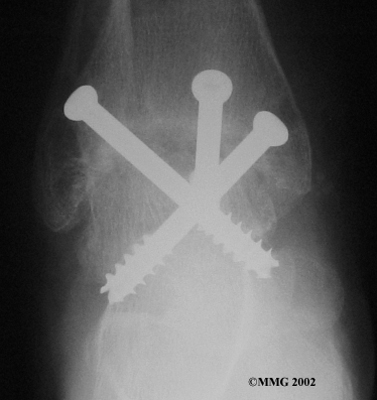

Your ankle will be bandaged with a well-padded dressing and a splint for support after surgery. Most patients are instructed not to place weight on their foot for a period of time after surgery. After arthroscopy, this period typically lasts about one week. Although recovery time is not the same for everybody, after ankle joint replacement, most patients are usually advised to avoid placing weight on their foot for up to 12 weeks.